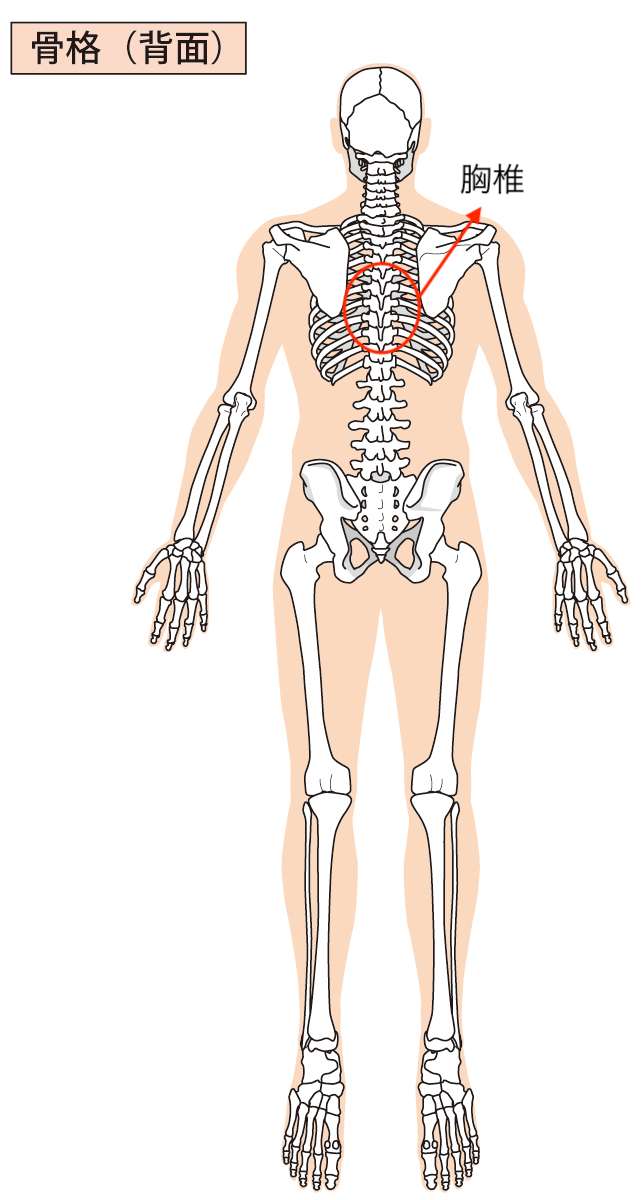

動きをチェックしてから全身の状態を検査していくと、胸椎(背骨)の歪みと横隔膜の硬さがありました。

一枚目の画像では、胸椎(背骨)の歪みがあった場所を示してあります。

また、先ほどお伝えした胸椎(背骨)の部分にこの横隔膜がくっついているので、その影響もあって胸椎が歪んでいたことがわかりました。

ご相談いただいた方の場合は、胸椎の部分と横隔膜に特に問題があったので、自宅でできるセルフケアとして「胸椎(背骨」と「横隔膜(溝落ち)」を温めることからはじめていただくようにお伝えさせていただきました。

今回ご相談いただいた方の場合だと肩こりだから「肩」というわけではなくて、「胸椎」と「横隔膜」だったわけです。